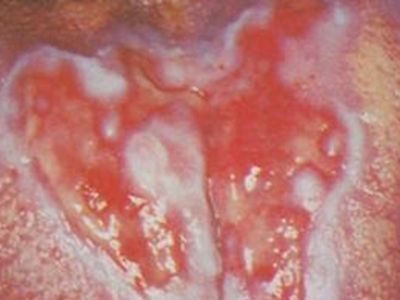

口癣一般指口腔扁平苔藓,是累及口腔,与细胞介导免疫功能紊乱有关的慢性炎症性疾病。好发于中年人,且女性多于男性,通常病程较长。患病后,临床特征为口腔黏膜损害,早期没有自觉症状,也容易被忽视,多在检查时偶然发现,其具体病因不明,通常在治疗时也需给予药物治疗及生活调理。

口癣的临床特征为口腔黏膜损害,主要为珠光白色条纹或网纹,也可为单线条或绕成环形。在舌背多为圆形或椭圆形白色斑块,损害区乳头消失而平伏。软腭或其他部位可发生透明颗粒状水疱。条纹之间的黏膜色泽可以正常或充血;有时在损害范围内某一区域发生糜烂,在唇部或颊黏膜处有时可出现针头大小、微隆的丘疹。